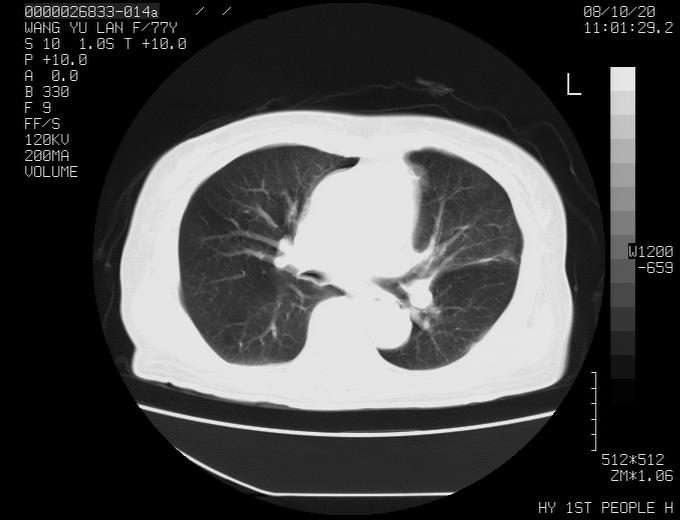

女性,77岁,胸部疼痛半月。左上肺团块影,本人考虑血管畸形,请分析

左上叶前段多发结节肿块并前段支气管息肉样结节、上叶腋亚段阻塞性肺炎,以结核可能性大。

纵隔有多个淋巴结肿大,提示周围型肺癌并转移可能性大。

1、考虑avm可能性大。2、纵隔有肿大淋巴结,左肺上叶有炎性病变,不排除肺癌并转移可能。